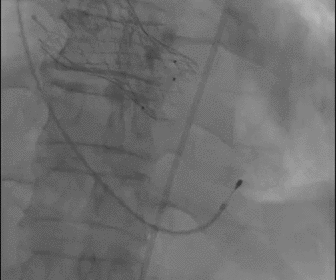

根部造影

球囊预扩